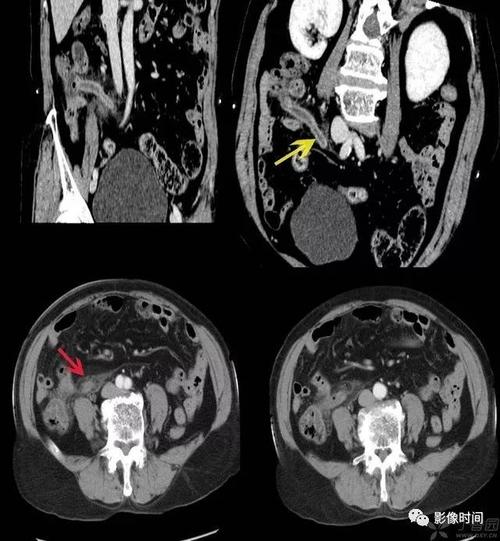

文摘:高位急性阑尾炎的临床及 ct 诊断分析

急性阑尾炎的ct表现

打基础急性阑尾炎ct诊断